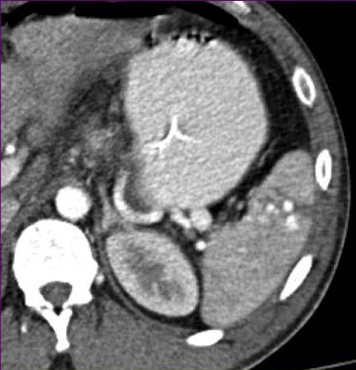

脾创伤的CT特征和非手术治疗的失败率增加有关,决定这类病人是否需要紧急的血管造影或栓塞,甚至是外科手术【3】。其中最重要的两条是活动性出血的象征,造影剂外溢和脾血管损伤的证据如假性动脉瘤、损伤后动静脉瘘。 造影剂外溢 造影剂外溢的表现:不规则和线样造影剂外溢出现在脾实质或包膜下间隙。

脾血管损伤:假性动脉瘤,外伤后动静脉瘘。在动脉期很难和活动性出血鉴别,但延时期会消失(wash-out)。